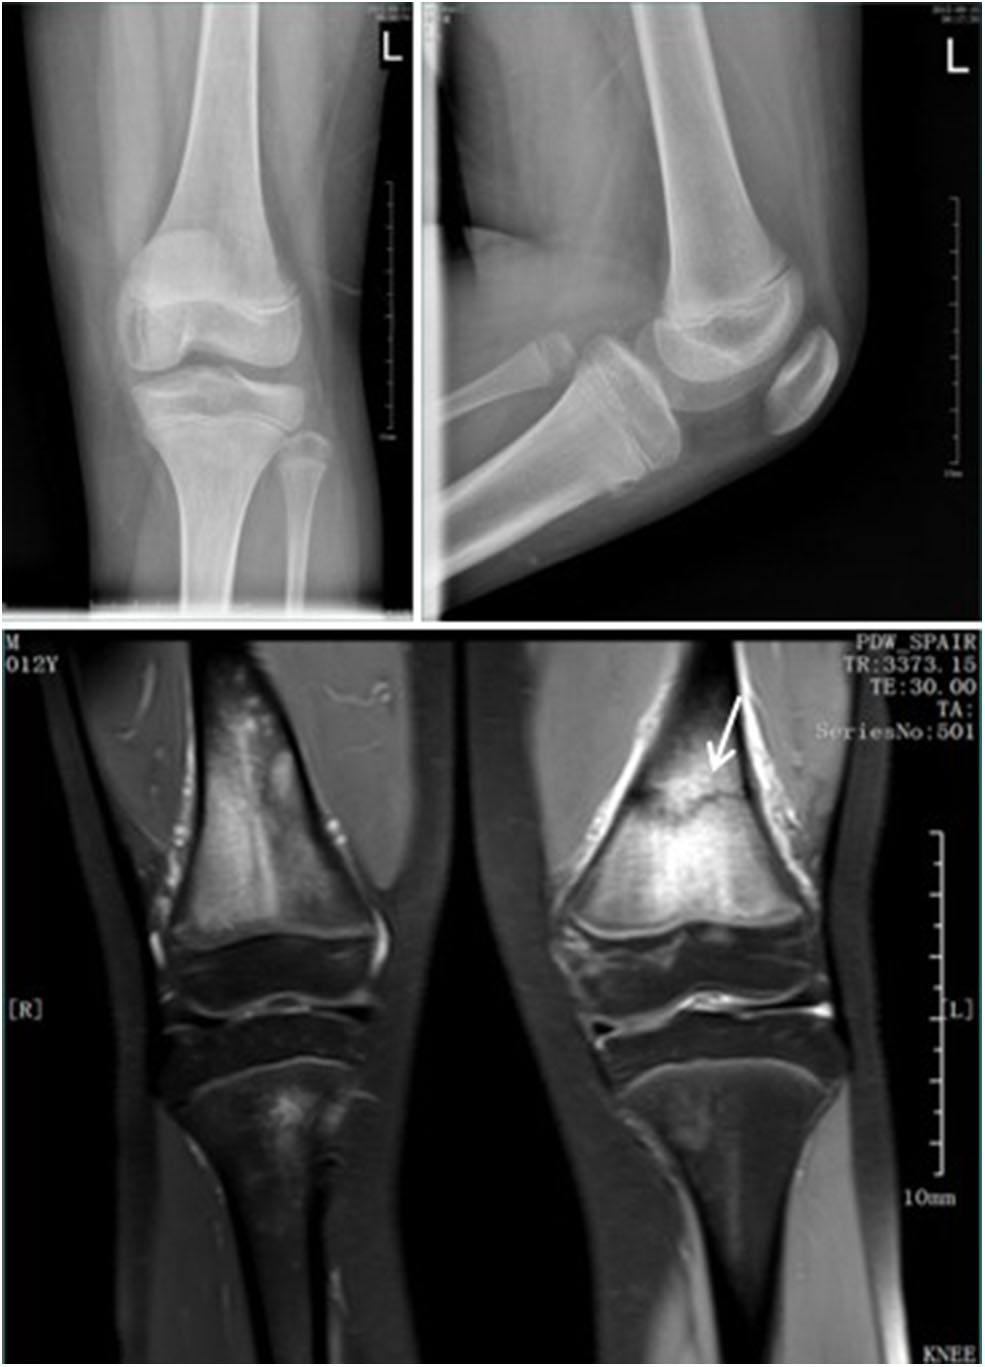

A total of 43,560 pediatric patients with AEI were enrolled, of whom 5,466 patients were diagnosed with fracture, 4,916 of which were confirmed by initial plain radiographs, and 550 were occult fractures confirmed by immediate MRI, immediate CT, or late radiographs 2 weeks post-injury. The mean age of the occult fracture patients was 7.9 years (range 1.6–14 years). The distribution of fractures diagnosed by initial plain radiographs and the distribution and rate of occult fractures in the extremities is summarized in Table 1. The prevalence of occult fractures of the extremities was 10.1% (550/5,466). The history and physical examination findings of all 550 patients led the orthopedic surgeons to suspect a possible fracture although there were no visible signs of fracture on the initial anteroposterior and lateral radiographs. Immediate MRI (n = 193) (Figure 1), immediate CT (n = 199) (Figure 2), or late radiographs (n = 158) (Figure 3) finally confirmed these occult fractures. The physical examination of the 550 patients revealed abnormal soft tissue swelling, persistent pressure pain at the trauma site, and limited active and passive motion because of pain. For patients with distal humerus injury, their anteroposterior and lateral radiographic views showed displacement of the fat pads (fat pad sign) due to joint effusion, which is an indirect sign of fracture (Figure 4).

FIGURE 3

www.frontiersin.org

Figure 3. Standard radiograph in AP and LL projections. Fractures were not visible at the first visit. After 3 weeks, a healing line (arrow) could be seen clearly.